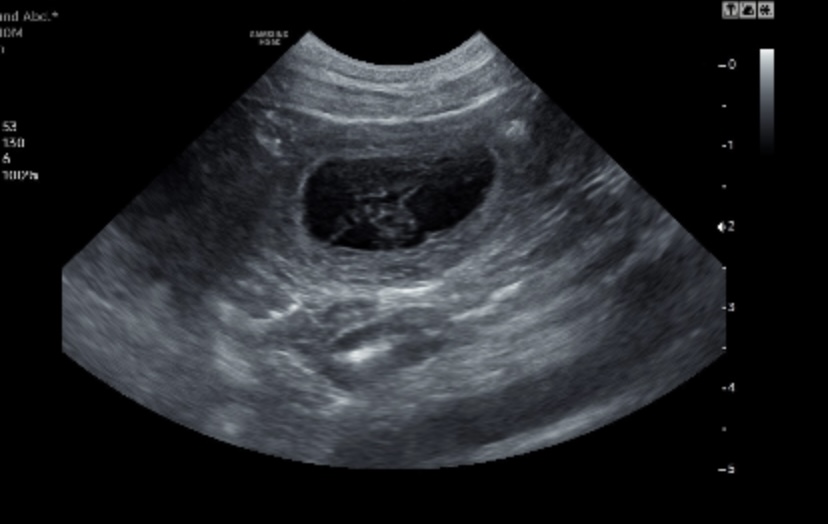

Jagdlicher Nachwuchs in Sicht

Der Ultraschall hat es bestätigt: Hedda vom Landgöding ist tragend – es sind mindestens 6 Fruchtanlagen zu erkennen. Juhu! Die kleinen Herzen schlagen…